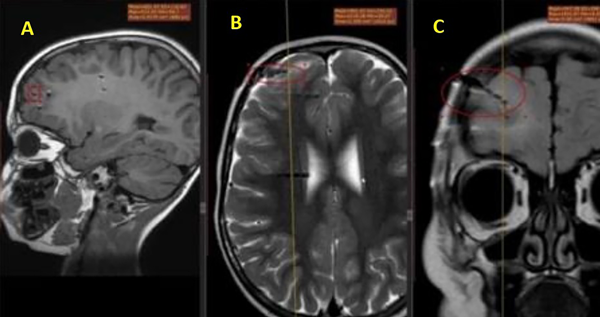

La colocación de electrodos EEG profundos es una de las técnicas adicionales utilizadas para el diagnóstico de epilepsia temporal, especialmente en situaciones donde el córtex funcional contiene la zona de resección prevista. La región definida por los electrodos profundos colocados en el cerebro es la salida del EEG desde la materia gris profunda, que es inaccesible para los electrodos superficiales. Los electrodos fueron instalados debido a uno o varios de los siguientes factores: incapacidad para localizar con precisión el sitio de inicio del ataque usando un EEG superficial, sospecha de inicio de epilepsia multifocal e inconsistencia entre los datos de RM y monitoreo de EEG con video.12,13 Las complicaciones con la colocación de electrodos profundos, como la hemorragia intracerebral, ocurren en el 1-4% de los casos y raramente son fatales.14 Además, tuvimos dificultades para identificar la etiología de la epilepsia en 5 individuos porque no se encontraron anormalidades patológicas cerebrales en la RM que pudieran explicar indirectamente la epilepsia (foco RM-negativo).15 Además, el monitoreo de EEG con video fue ineficaz en estos casos.16 Estos pacientes recibieron la instalación de electrodos profundos para localizar el centro epiléptico debido a los desafíos diagnósticos mencionados anteriormente, lo que hizo imposible realizar un tratamiento quirúrgico adecuado (Figura 2, 3 y 4).17,18

Figura 4. Ejemplo de los electrodos profundos instalados en una RM en cortes axiales (A), coronales (B) y sagitales (C).